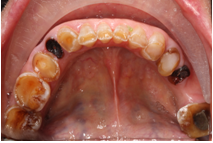

2、龋病

老年朋友根面龋比较常见。龋病在最初的时候往往没有什么症状,出现疼痛就诊时可能已经需要行去神经根管治疗了。而很多患者朋友却不在意,任龋患发展,待到就诊时牙齿很多时候都需要拔除了。治疗龋病的策略是早发现早治疗。病情进展到需要根管治疗后往往还需要修复科行冠修复,时间和经济都是种损失。而任龋病进展到需要拔牙的程度就得不偿失了。